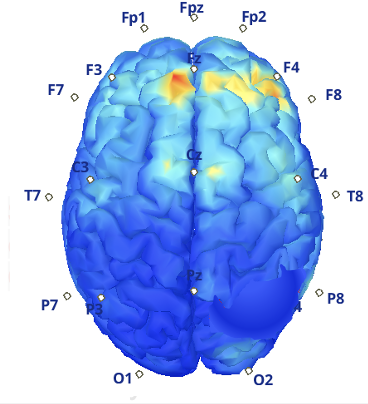

This EMU Science Program focuses on developing and implementing advanced computational tools for signal and multimodal data analysis, with the goal of improving the interpretation and clinical utility of the data collected during patient monitoring. By harnessing the power of sophisticated signal processing techniques, neuroimaging and data science, the program aims to provide deeper insights into the complex brain activity associated with epilepsy.

Through the integration of these innovative tools into the daily operations of the EMU, the EMU-SDS Program seeks to help clinicians localize epileptiform EEG patterns, refine diagnoses, and personalize treatment strategies more effectively. The ultimate objective is to improve patient outcomes by making the monitoring process more efficient, accurate, and actionable, enabling timely interventions and optimizing care for individuals with epilepsy.